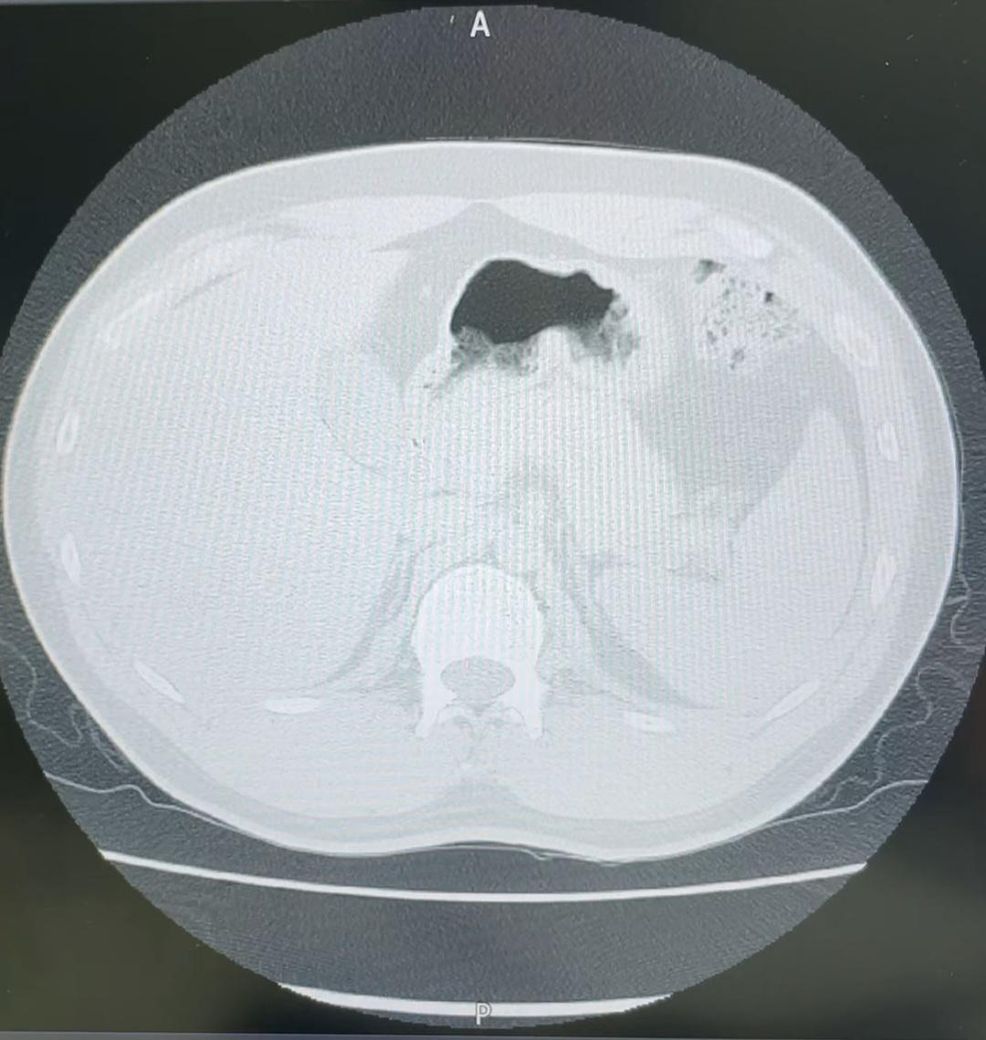

의사 소견상에 a small nodule in LLL (#2/65)

이렇게 나와있는데 주변에 의사분이 계셔서 물어보니 65번째 사진상에 2개의 작은 결절이 보인다고 해석 한거 같은데 주변 의사선생님 말로는 이상 없다고 하시는데 다른 의사분들의 해석이 궁금합니다.

사진은 CT 사진중 65번째 사진입니다.

a small nodule in LLL (#2/65) 은 2번 시리즈 영상의 65번째 컷에서 확인할 수 있으며, 좌측 아래 폐에 작은 폐결절이 보인다는 내용입니다.

올려주신 사진은 폐가 보이지 않고 간과 비장이 보임으로 미루어 볼때 2번 시리즈가 아닌, 다른 시리즈의 65번째 컷이 아닐까 조심스럽게 예상해봅니다.

재확인이 필요할 것 같습니다.